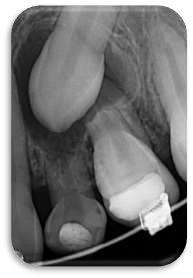

Hallazgos radiográficos:

La ortopantomografía revela:

Dos supernumerarios de morfología cónica en la región interincisal superior

Ambos mesiodens erupcionados, en coexistencia con los incisivos centrales permanentes.

Ausencia de patología periapical o lesiones radiolúcidas asociadas

Pieza 2.1 y 1.1. 2.2 1.2 con mesioversion

Presencia germen dentario piezas 8

Doble mesiodens erupcionado en región anterosuperior, coexistiendo con incisivos centrales permanentes erupcionados y sin diastema.

FIGURA 2 (PERIAPICAL PZA. 1.3)